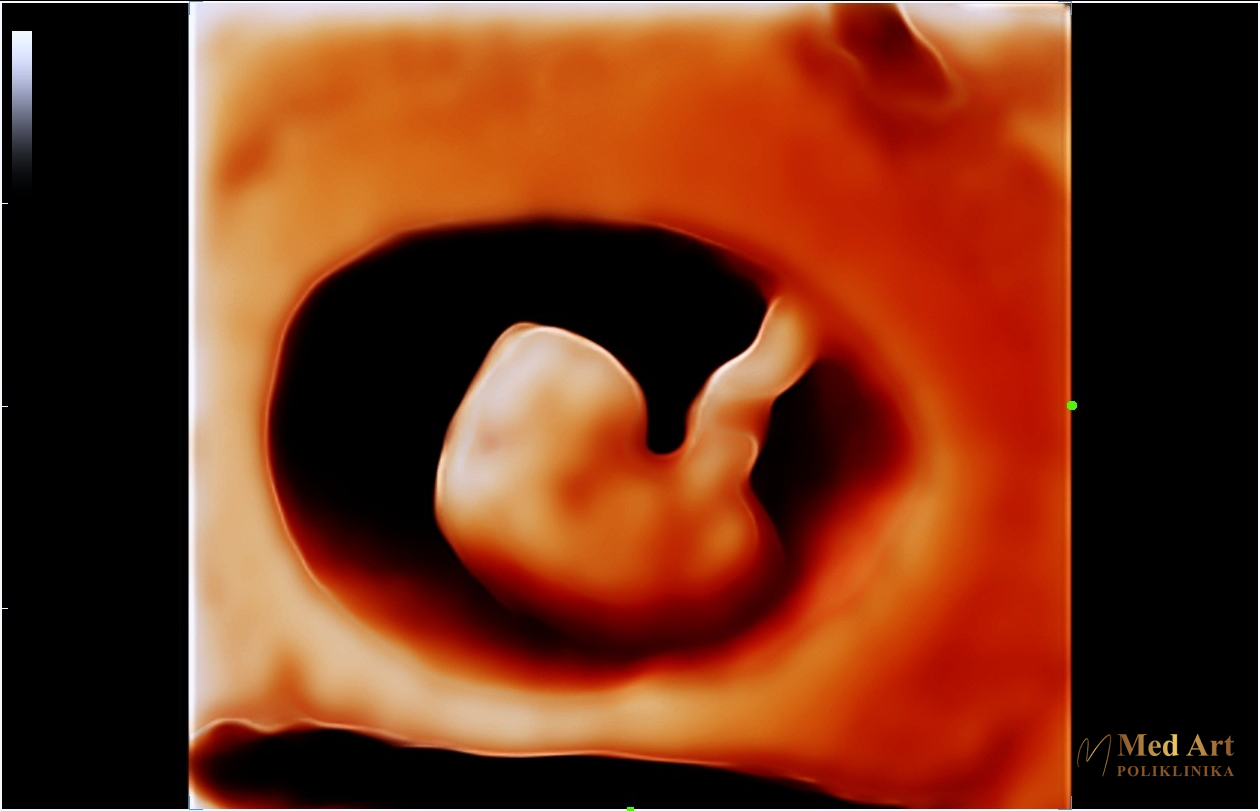

U galeriji koja slijedi, možete vidjeti ultrazvučne slike beba u 6., 7., 8., 12., 14., 20., 21., 24., 27. i 34. tjednu trudnoće, koje prikazuju njihov razvoj od rane trudnoće pa sve do priprema za dolazak na svijet.